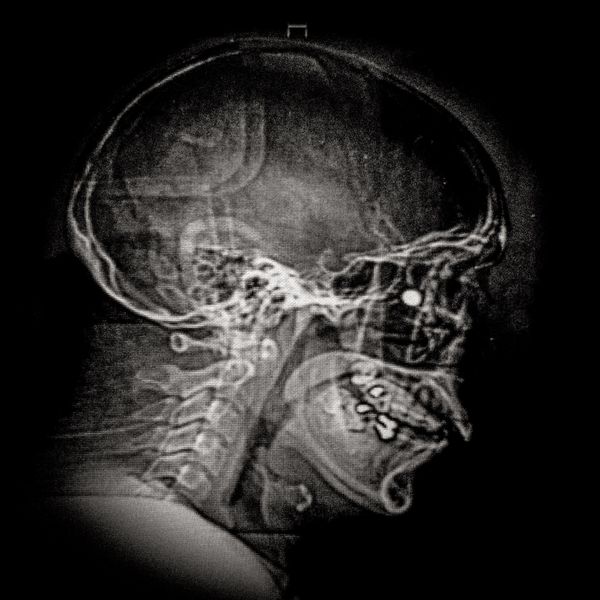

X ray showing the embedded pellet of an injured man during Santiago protests.